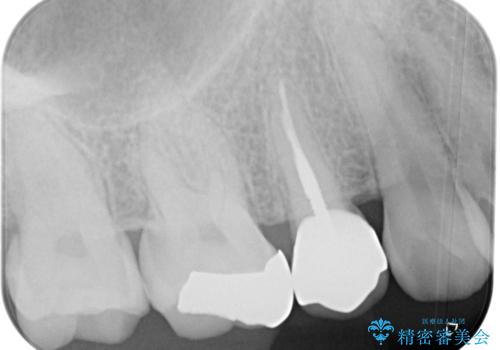

- 笑うときに目立つ銀歯を白くしたいとのことで来院された患者様です。

奥歯ではありますが、以前抜歯矯正をされているので前の方へ移動しており、非常に目立っていました。

仮歯に替えた上で、速やかにオールセラミッククラウンにて補綴治療を行うこととしました。

銀歯を外したところ、土台にほとんどむし歯はなかったため、土台のやり替えを行うことなく、セラミッククラウンを装着しました。